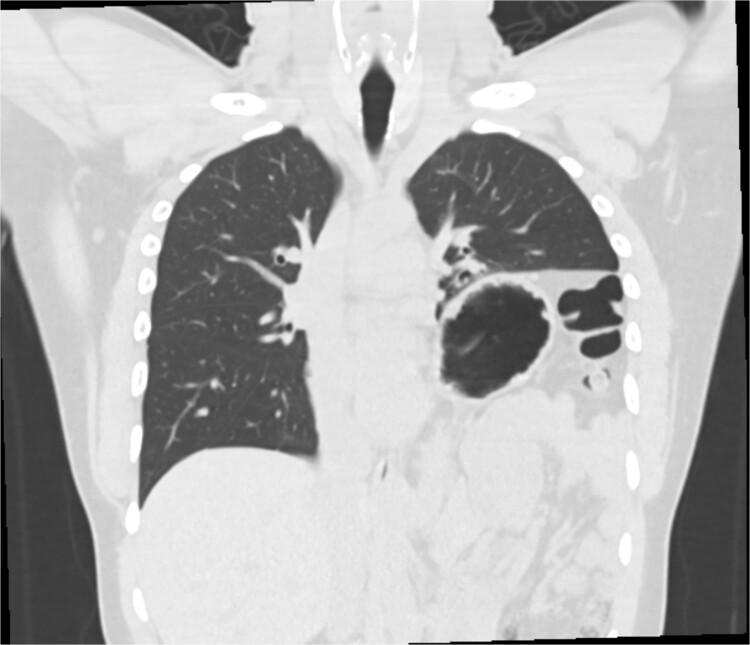

Gastric volvulus has been rarely associated with diaphragmatic paralysis or eventration. In this article, we present the case of a patient with idiopathic paralysis of the left hemidiaphragm that underwent treatment with a robotic thoracoscopic diaphragm plication, which was complicated by massive gastric volvulus resulting in such significant intra-abdominal hypertension that the ipsilateral diaphragm ruptured anterior to the plication suture line.

胃扭转很少与膈麻痹或膈膨出相关。在本文中,我们报告了一例特发性左半膈麻痹患者,该患者接受了机器人胸腔镜膈折叠术治疗,术后并发大量胃扭转,导致严重的腹腔内高压,使得同侧膈肌在折叠缝线前方破裂。